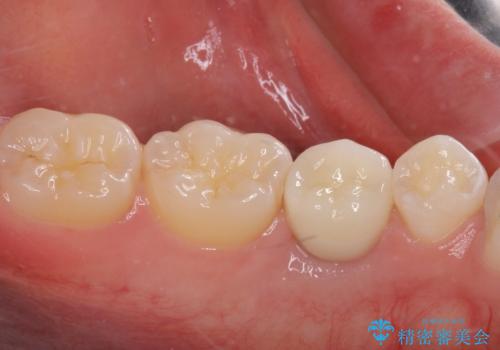

矯正治療が終わるタイミングに合わせてインプラントの埋入を行っていたので、矯正治療を終了すると同時にセラミック補綴治療を行えました。

短期間でしっかりと治療を終えることができました。